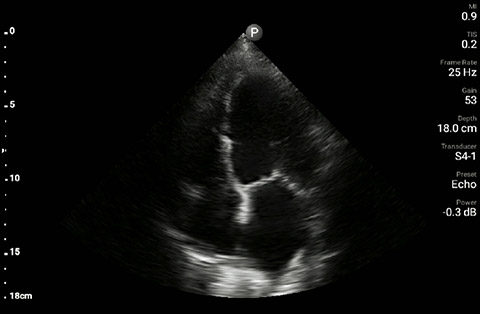

The patient had reduced LV systolic function without new or severe valvular pathology, a dilated, non-collapsing IVC, and diffuse B lines (left greater than right) on lung ultrasound imaging.

Apical 4-chamber